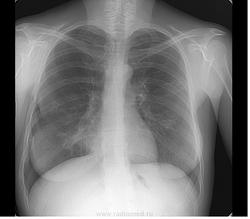

Пол пациента: Мужской пол Тип патологии: Другое Область исследования: Грудная клетка и верхние дыхательные пути Методы исследования: Другие Ж, 1976г. М, 1980 Скорее всего оба случая будут пропущены через туб. диспансер. Хотелось бы услышать ваши предварительные заключения) https://radiomed.ru/sites/default/files/styles/case_slider_image/public/user/5536/klementmd_82009_1.jpg?itok=rsgLS6s_ https://radiomed.ru/sites/default/files/styles/case_slider_image/public/user/5536/klementmd_82010_1.jpg?itok=1UPMmGH6 https://radiomed.ru/sites/default/files/styles/case_slider_image/public/user/5536/klementmd_82008_1.jpg?itok=wyVmKRJh ID:21496 Втр, 29/05/2012 - 22:06 #1 Катенёв Валенти... Не на сайте Был на сайте: 7 лет 3 недели назад Зарегистрирован: 22.03.2008 - 22:15 Публикации: 54876 Если Ж, последние три снимка, то необходима правая боковая томография в срезах 5,7,9 см. Втр, 29/05/2012 - 22:08 #2 Mitkampfer Не на сайте Был на сайте: 11 лет 1 месяц назад Зарегистрирован: 27.07.2010 - 07:43 Публикации: 1454 Ж. - первый снимок. Томография выполняется в тубдиспансере. Не ограничивайте свою мысль Живешь пока учишьсяEcrasez l’infame Втр, 29/05/2012 - 22:09 #3 Катенёв Валенти... Не на сайте Был на сайте: 7 лет 3 недели назад Зарегистрирован: 22.03.2008 - 22:15 Публикации: 54876 Линейная томография выполняется только в туб диспансере? Втр, 29/05/2012 - 22:10 #4 Mitkampfer Не на сайте Был на сайте: 11 лет 1 месяц назад Зарегистрирован: 27.07.2010 - 07:43 Публикации: 1454 ну у нас только цифровой флюорограф на станции) На дальнейшее дообследование отправляем в наш тубдиспансер. Не ограничивайте свою мысль Живешь пока учишьсяEcrasez l’infame Втр, 29/05/2012 - 22:11 #5 Катенёв Валенти... Не на сайте Был на сайте: 7 лет 3 недели назад Зарегистрирован: 22.03.2008 - 22:15 Публикации: 54876 А. что за "станция"? Втр, 29/05/2012 - 22:12 #6 Mitkampfer Не на сайте Был на сайте: 11 лет 1 месяц назад Зарегистрирован: 27.07.2010 - 07:43 Публикации: 1454 флюоростанция Не ограничивайте свою мысль Живешь пока учишьсяEcrasez l’infame Втр, 29/05/2012 - 22:19 #7 Катенёв Валенти... Не на сайте Был на сайте: 7 лет 3 недели назад Зарегистрирован: 22.03.2008 - 22:15 Публикации: 54876 Понятно. И, Вы работаете только на флюоростанции, или еще в рентгенодиагностике? Втр, 29/05/2012 - 22:22 #8 Mitkampfer Не на сайте Был на сайте: 11 лет 1 месяц назад Зарегистрирован: 27.07.2010 - 07:43 Публикации: 1454 На флюоростанции я совмещаю. но мы отвлеклись от темы) Не ограничивайте свою мысль Живешь пока учишьсяEcrasez l’infame Втр, 29/05/2012 - 22:24 #9 Катенёв Валенти... Не на сайте Был на сайте: 7 лет 3 недели назад Зарегистрирован: 22.03.2008 - 22:15 Публикации: 54876 Флюорограмма есть, патология есть, слово за томографией (в рентгеновском векторе). Втр, 29/05/2012 - 22:32 #10 Nikolas Не на сайте Был на сайте: 2 месяцев 9 часов назад Зарегистрирован: 21.12.2010 - 20:37 Публикации: 4559 случайные? Втр, 29/05/2012 - 22:42 #11 И.Бондаренко Не на сайте Был на сайте: 2 дня 6 часов назад Зарегистрирован: 13.09.2011 - 22:55 Публикации: 9206 В первом случае может что-то похуже выскочит. Во втором, в ПТД, возможно и пневмония. Ср, 30/05/2012 - 06:50 #12 Vikkur Не на сайте Был на сайте: 4 года 8 месяцев назад Зарегистрирован: 24.09.2009 - 14:34 Публикации: 1749 Ж архив, может и пост. измен, М в ПТД Виктор. Ср, 30/05/2012 - 13:20 #13 stovbav Не на сайте Был на сайте: 2 года 2 месяцев назад Зарегистрирован: 20.12.2009 - 17:28 Публикации: 7066 У Ж еще и 7-8-е ребра справа сломаны, причем - не очень давно)))) Болезни ног: виды, симптомы, причины, профилактика и лечение Ср, 30/05/2012 - 19:23 #14 Вылегжанина Юли... Не на сайте Был на сайте: 11 лет 5 месяцев назад Зарегистрирован: 15.05.2012 - 22:09 Публикации: 55 томография и направление в туб диспансер ,но там скорее всего поставят пневмонию и контроль после лечения Вылегжанина Юлия Ср, 30/05/2012 - 20:05 #15 Nikolas Не на сайте Был на сайте: 2 месяцев 9 часов назад Зарегистрирован: 21.12.2010 - 20:37 Публикации: 4559 комментарий, но не уверен в получении конечного результата, чтобы проверить правильность высказанных суждений. Ср, 30/05/2012 - 21:26 #16 Mitkampfer Не на сайте Был на сайте: 11 лет 1 месяц назад Зарегистрирован: 27.07.2010 - 07:43 Публикации: 1454 обоих направил в тубдиспансер результат должен быть. У Ж. плохой анамнез - наркомания, состояла на учете в ПТД какое то время, тбс не обнаружилось. У М. - нет жалоб. Не ограничивайте свою мысль Живешь пока учишьсяEcrasez l’infame Ср, 30/05/2012 - 21:43 #17 Mitkampfer Не на сайте Был на сайте: 11 лет 1 месяц назад Зарегистрирован: 27.07.2010 - 07:43 Публикации: 1454 stovbav wrote: У Ж еще и 7-8-е ребра справа сломаны, причем - не очень давно)))) согласен) +9 Не ограничивайте свою мысль Живешь пока учишьсяEcrasez l’infame

В первом случае может что-то похуже выскочит. Во втором, в ПТД, возможно и пневмония.

Ж архив, может и пост. измен, М в ПТД

томография и направление в туб диспансер ,но там скорее всего поставят пневмонию и контроль после лечения

обоих направил в тубдиспансер результат должен быть. У Ж. плохой анамнез - наркомания, состояла на учете в ПТД какое то время, тбс не обнаружилось. У М. - нет жалоб.